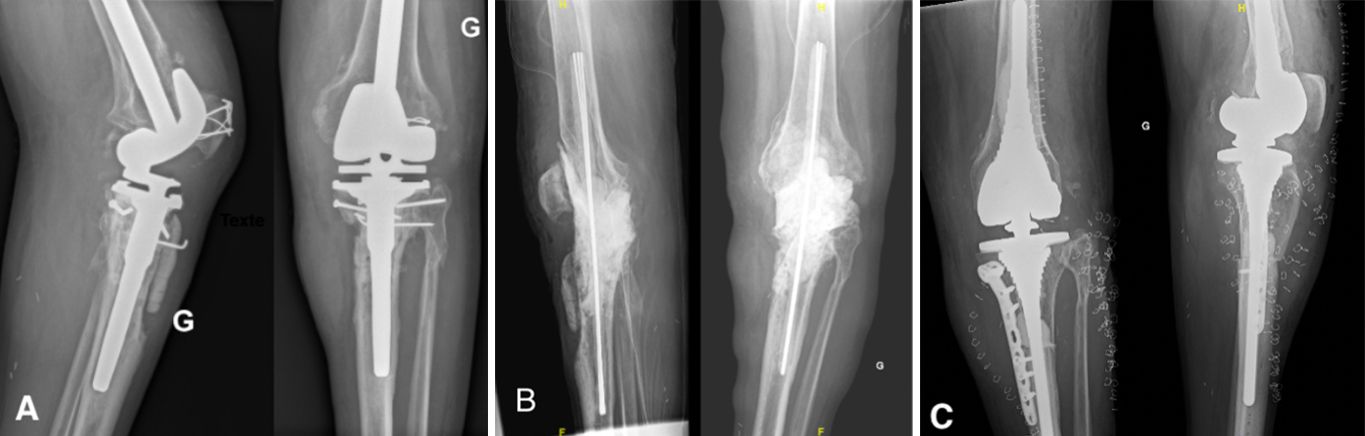

The issue's clinical contributions center on the diagnosis and management of orthopedic infection. Epidemiological and microbiological dimensions are addressed through a 5-year retrospective investigation of septic arthritis of the knee in Azerbaijan, complemented by therapeutic guidelines for joint arthroplasty in sequelae of septic hip arthritis. Operative strategies including static spacers in periprosthetic knee infections, antibacterial implant coating, and a novel DTT-based diagnostic approach to biofilm-related infections further define the issue's scientific scope.